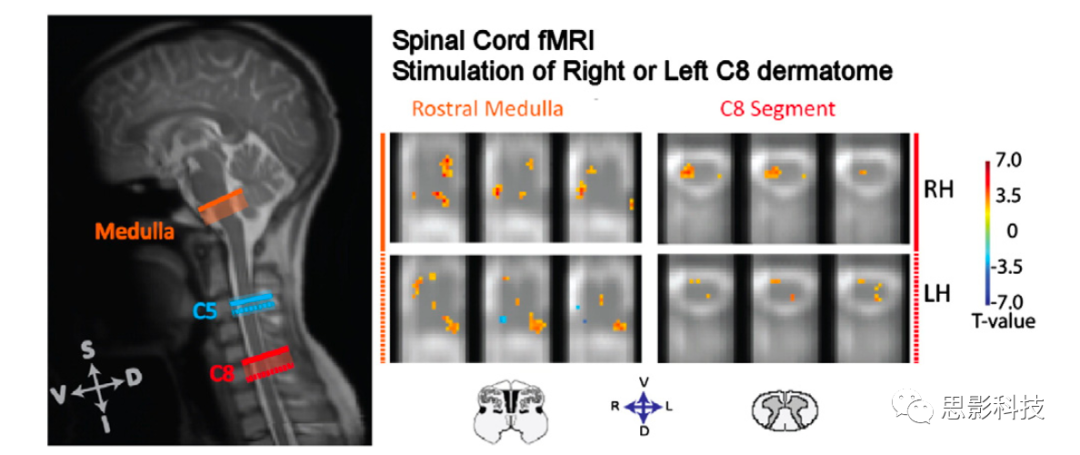

4、NeuroImage:脊髓成像方法论述

本文记录了在2013年首届脊髓影像学会议的讨论意见,在会上脊髓影像学领域的专家学者对当时先进的脊髓研究方法与技术以及面临的挑战进行了交流与讨论。在脊髓影像学研究中最大的挑战就来源于脊髓本身,首先脊髓被骨骼重重包围,其次会受到周围脊柱与组织的运动的影响,最重要的就是其在横截面上过小的尺寸,都加大了脊髓成像中的困难,而且脊髓损伤患者常会植入金属用于固定患处而更加难以在核磁设备中进行采集。另一挑战则在于研究人员的匮乏,由于缺少大量研究人员进行脊髓的研究,即影响了脊髓影像学的研究进展,也由于缺乏需求而影响设备生产商对于相关设备研发的积极性。并在当时确定相对先进的研究方法,对潜在的理论与挑战进行讨论,分析这些方法在当时以及后来的发展中的潜在影响。在研究方法上提出将功能磁共振成像(fmri),弥散张量成像(dti)以及正电子发射断层成像(PET)等技术应用与脊髓研究的实例;在面对的挑战上,对于动作对于数据采集的影响以及解决方法,脊髓影像的配准方法等等方面展开讨论。基于这些研究人员的讨论结果,后续脊髓影像学的研究有了更加明确的发展方向。